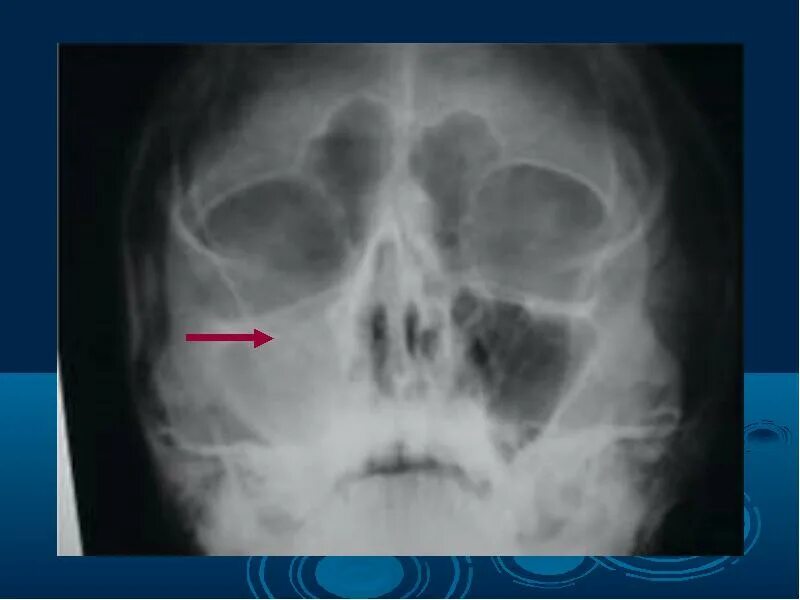

Двухсторонний верхнечелюстной синусит у ребенка